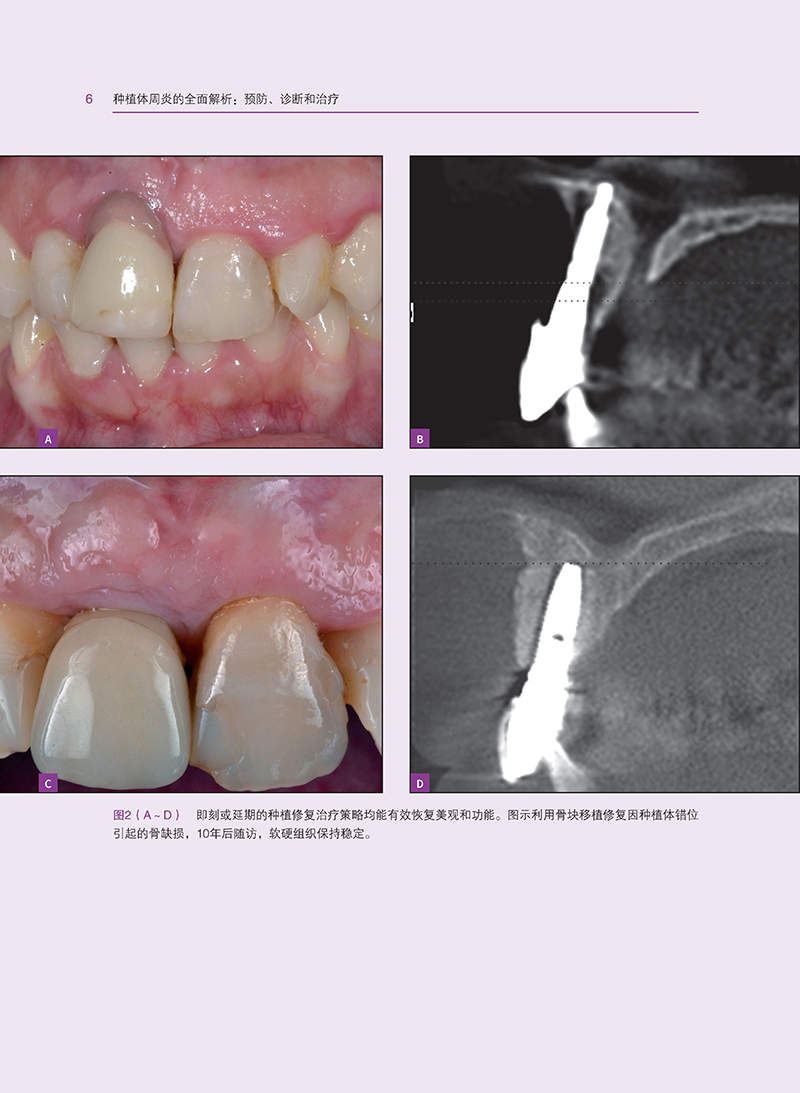

本书全面解析了种植体周炎的发生和发展相关问题,从诊断与监测到治疗策略,涵盖了种植体周炎的各个方面。首先,深入探讨了种植体周炎的形态学和表型特征,为读者提供了清晰的认识基础。接着,详细分析了种植体周炎的理想三维软组织和硬组织量,以及影响种植体周炎的局部风险因素、全身因素和不良习惯。同时,本书还介绍了遗传学和表观遗传学对种植体周炎的影响,为深入理解种植体周炎的发病机理提供了新的视角。

在治疗方面,本书从初级预防和次级预防两个层面出发,详细阐述了种植体周炎的预防策略。同时,结合牙周炎治疗的经验,提出了种植体周炎的管理策略,包括非手术治疗、药物联合治疗和手术治疗等。此外,本书还介绍了种植体表面去污策略,以及手术治疗的时机选择,为读者提供了实用的治疗建议。